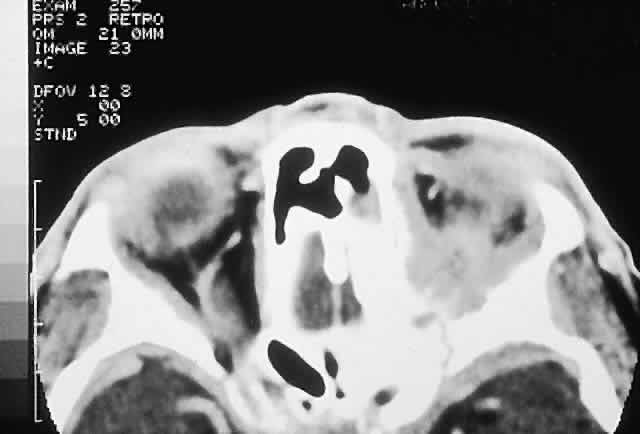

Bone metastases with a bony epicenter may more commonly create confusion with primary orbital bone tumors. Clinically, they tend to have a more rapid course featuring pain, mass effect, and infiltration. Radiologically, they are classified as osteolytic, mixed, or osteoblastic. Most are osteolytic or mixed. However, metastases from prostate and carcinoid usually result in osteoblastic lesions (Fig. 14). Breast, lung, gastrointestinal, and renal metastases may also be osteoblastic, but this is uncommon. Hyperostotic meningiomas have been discussed previously.

Fig. 14. CT from a 21-year-old man with prostatic cancer demonstrated osteoblastic metastasis affecting the left greater wing of the sphenoid and ethmoid bones.